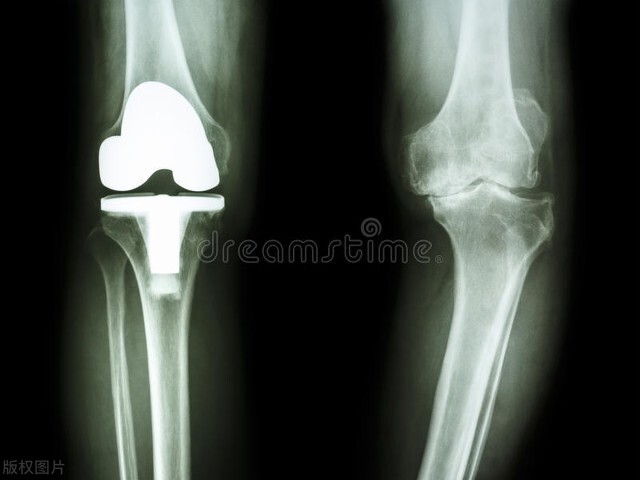

人工膝关节置换手术后,一个月时间里度日如年

人老先老腿。随着右膝关节的病变,我不得不接受人工关节置换手术。